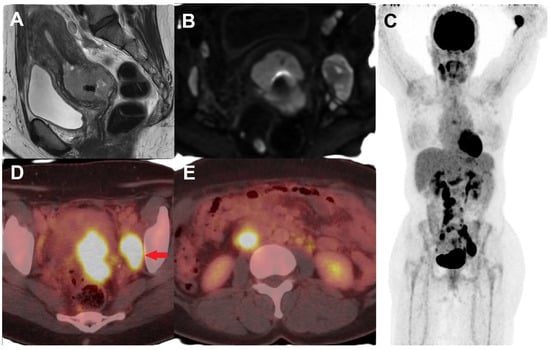

3. FDG PET/MR in Cervical Cancer

- Tarcha, Z.; Konstantinoff, K.S.; Ince, S.; Fraum, T.J.; Sadowski, E.A.; Bhosale, P.R.; Derenoncourt, P.-R.; Zulfiqar, M.; Shetty, A.S.; Ponisio, M.R.; et al. Added Value of FDG PET/MRI in Gynecologic Oncology: A Pictorial Review. RadioGraphics 2023, 43, e230006. [Google Scholar] [CrossRef] [PubMed]

- Zhu, Y.; Shen, B.; Pei, X.; Liu, H.; Li, G. CT, MRI, and PET Imaging Features in Cervical Cancer Staging and Lymph Node Metastasis. Am. J. Transl. Res. 2021, 13, 10536–10544. [Google Scholar]

- Tian, T.; Ren, J. Diagnostic Value of [18F]FDG PET/MRI in the Detection of Lymph Node Metastasis of Cervical Cancer: A Meta-Analysis. Clin. Transl. Imaging 2024, 12, 827–836. [Google Scholar] [CrossRef]

- Shih, I.-L.; Yen, R.-F.; Chen, C.-A.; Cheng, W.-F.; Chen, B.-B.; Chang, Y.-H.; Cheng, M.-F.; Shih, T.T.-F. PET/MRI in Cervical Cancer: Associations Between Imaging Biomarkers and Tumor Stage, Disease Progression, and Overall Survival. J. Magn. Reson. Imaging 2021, 53, 305–318. [Google Scholar] [CrossRef]